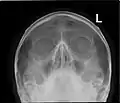

![]() Lateral projection of the paranasal sinuses | |

Paranasal sinuses are a group of four paired air-filled spaces that surround the nasal cavity.[1] The maxillary sinuses are located under the eyes; the frontal sinuses are above the eyes; the ethmoidal sinuses are between the eyes and the sphenoidal sinuses are behind the eyes. The sinuses are named for the facial bones and sphenoid bone in which they are located. Their role is disputed and no function has been confirmed.

Humans possess four pairs of paranasal sinuses, divided into subgroups that are named according to the bones within which the sinuses lie. They are all innervated by branches of the trigeminal nerve (CN V).

- The maxillary sinuses, the largest of the paranasal sinuses, are under the eyes, in the maxillary bones (open in the back of the semilunar hiatus of the nose). They are innervated by the maxillary nerve (CN V2).[2]

- The frontal sinuses, superior to the eyes, in the frontal bone, which forms the hard part of the forehead. They are innervated by the ophthalmic nerve (CN V1).[2]

- The ethmoidal sinuses, which are formed from several discrete air cells within the ethmoid bone between the nose and the eyes. They are innervated by the ethmoidal nerves, which branch from the nasociliary nerve of the ophthalmic nerve (CN V1).

- The sphenoidal sinuses, in the sphenoid bone. They are innervated by the ophthalmic and maxillary nerve (CN V1 and V2).[2]